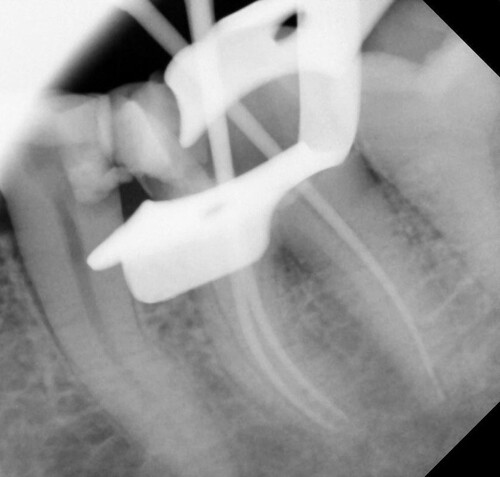

После введения местной анестезии, под изоляцией резиновой пломбой, отверстие доступа было изменено, и каналы были расположены. С помощью локатора апекса (Root ZX, J Morita, morita.com) рабочая длина была установлена на 1 мм короче рентгенографического апекса и подтверждена с помощью рентгенограммы (рис. 3).

Рис. 3